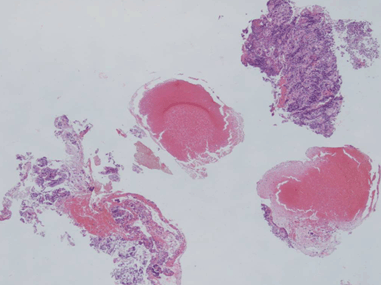

A 71-year-old male patient presented with constipation for one month. No rectal bleeding, pain or tenesmus were associated. Patient did not have a history of contact with or any symptoms of pulmonary tuberculosis. Physical examination was unremarkable, but digital rectal examination revealed hard annular growth about five cm from the anal verge. Colonoscopy showed annular thickening of lower rectum which was covered with a whitish patch. (Figure 1) On suspicision of malignancy, multiple biopsies were taken. Endorectal ultrasonography (B-K Medical HAWK 2102; 2050 anorectal radial probe and a 15 MHz transducer) demonstrated a hypoechoic lesion with pseudopodia. (Figure 2) Computed tomography confirmed a longitudinal circumferential rectal tumor suggestive of malignancy with multiple pelvic lymphadenopathy. (Figure 3) Endoscopic biopsy showed caseous necrosis with inflammatory cells which was suggestive of tuberculosis. (Figure 4) No malignant cells were seen. Chest X-ray showed active pulmonary tuberculosis with positive result for sputum acid fast stain. Anti-HIV ELISA was non-reactive. Serum carcinoembryonic antigen (CEA) was 4 ng/mL. Tissue acid fast stain and tissue culture for tuberculosis were negative. Standard six-month anti-tuberculosis medication was prescribed. The patient responded well to the treatment. His constipation improved. His rectal tumor had receded at the six- month endoscopic follow-up. | ||||||